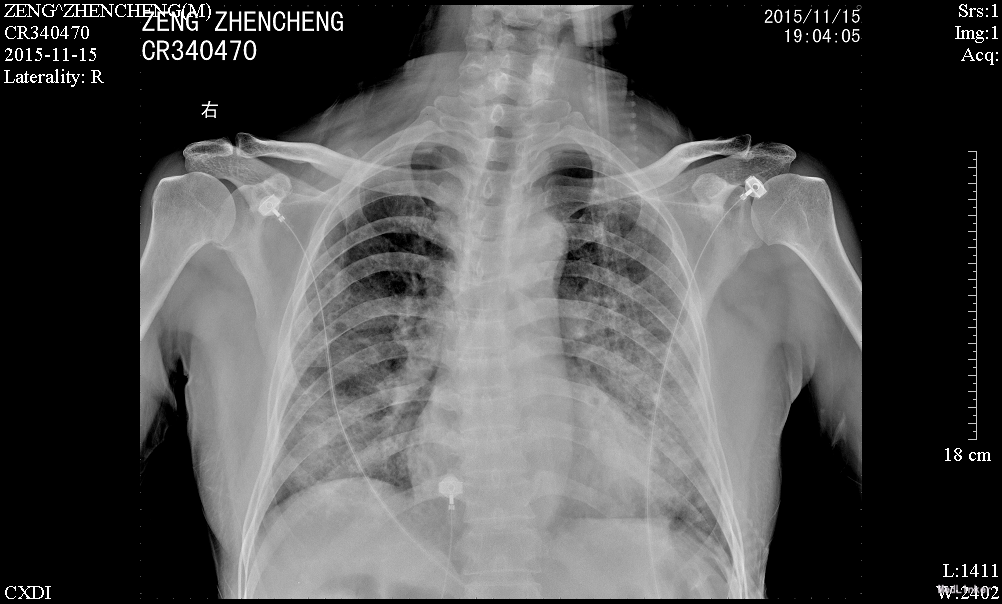

患者诉仍有咳嗽咳痰、呼吸困难、胸闷气促,咳白色粘痰,平卧及活动时加重,坐起后缓解,无发热,无咯血,精神、睡眠一般,饮食欠佳,大小便正常。高流量吸氧(7L/min)下血氧饱和度维持在93-95%,心率65-75次/分。查体:神志清楚,查体合作,胸廓未见异常;双肺呼吸音粗,双侧肺可闻及少许细湿罗音,无胸膜摩擦音;心界不大,心律齐,各瓣膜听诊区未闻及病理性杂音;腹平坦,无压痛、反跳痛,肝脏肋下未触及。辅助检查:感染三项:降钙素原(ProCT)6.00ng/ml;淀粉样蛋白A(SAA)281.8mg/L;C反应蛋白(CRP)。真菌D-葡聚糖(1_2_3βD)315pg/mL。巨细胞病毒定量(FQ_HCMV)2.85E+3copies/m。凝血功能:血浆D-二聚体测定(D-Dimer)0.85mg/L FEU;活化部分凝血活酶时间(APTT)46.8秒;血浆凝血酶原时间测定(PT)14.0秒。肾功能:尿素(BUN)19.52mmol/L;肌酐(CR)223μmol/L。肝功能:丙氨酸氨基转移酶(ALT)79U/L;天门冬氨酸氨基转移酶(AST)60U/L;总蛋白(TP)54.3g/L;白蛋白(ALB)21.8g/L150.67mg/L。前-脑利尿肽(Pro-BNP)572.1pg/mL。胸片示:1、两肺炎症,较前进展,建议治疗后复查;2、主动脉硬化;3、左肾区致密影,请结合临床其他检查;4、右第4肋骨陈旧骨折。